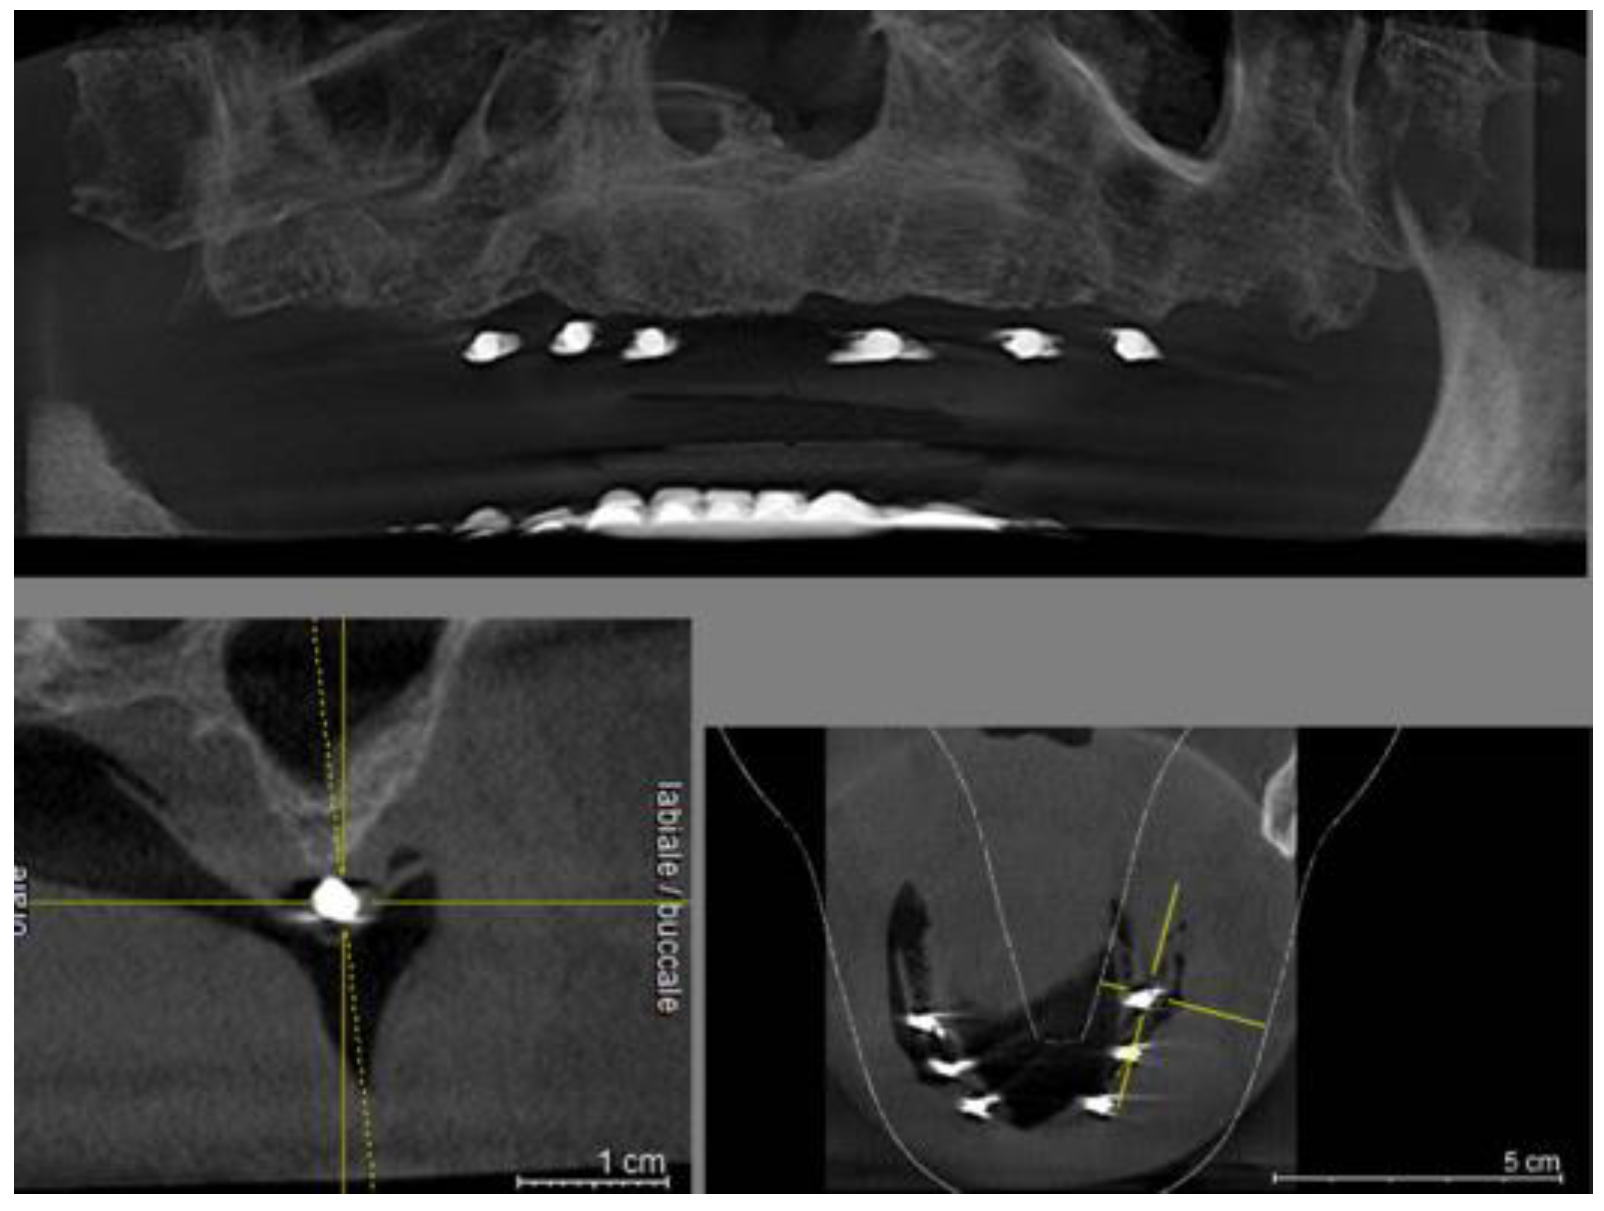

Figure 3. Panoramic view on CBCT.

Preprints 92994 g003

Figure 4. Cross section on CBCT.

Preprints 92994 g004

A total of 32 masks were thermoformed for each edentulous arch and CBCT was performed for all patients during which the masks with radiopaque references were worn.

Each individual CBCTs was analyzed by an expert implantologist in order to find the best sites where to place the implants.

For a total of 26 implant sites chosen in the panoramic radiograph, the preliminary site selection was confirmed; for the remaining 102 implants a different site was chosen on the CBCT.

During the free hand surgical phase, planned and performed by an expert operator with more than 20 years of experience, in order to best identify the implant sites chosen on the CBCT on the mucosa, the patients wore masks with radiopaque references.

A mark was made on the mucosa in correspondence with the radiographic landmark with an indelible felt-pen.

In this way, these signs, simulating certain and visible anatomical landmarks in the CBCT, have enormously facilitated the identification of the implant site on the cortex which is a very critical phase in the free hand technique (See Table 1).